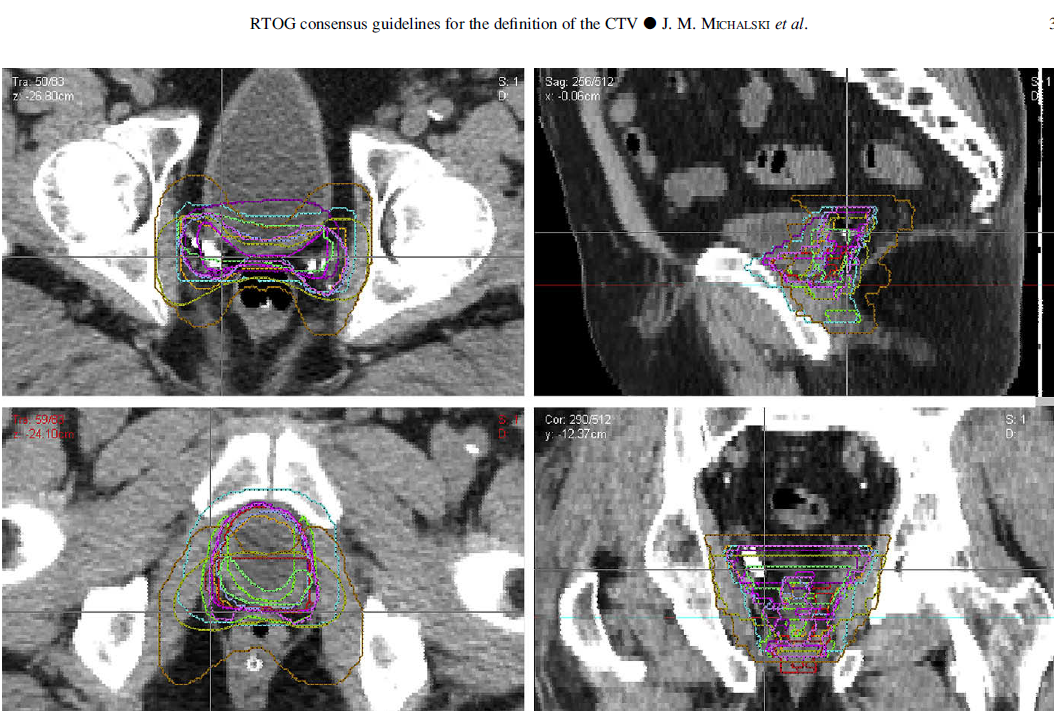

Even is the pelvis isn't treated physician contours are all over the map. Below are twelve independent "GU experts" CTV contour for a postop case.

1586820240142.png